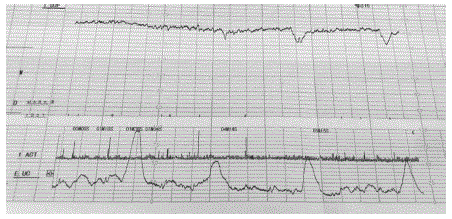

Gestante, 32 anos de idade, secundigesta com uma cesárea anterior, 40 semanas e 2 dias de gravidez. Refere contrações irregulares e redução de movimentação fetal há 1 dia. Ao exame clínico, bom estado geral, corada, PA 120x70mmHg, altura uterina 30 cm, BCF presente rítmico. Toque vaginal com colo grosso, posterior, impérvio.

Vitalidade fetal: tônus adequado, movimentação corpórea e respiratória presentes, índice de líquido amniótico de 4,2 cm. Cardiotocografia apresentada.

Qual é a conduta adequada neste momento?